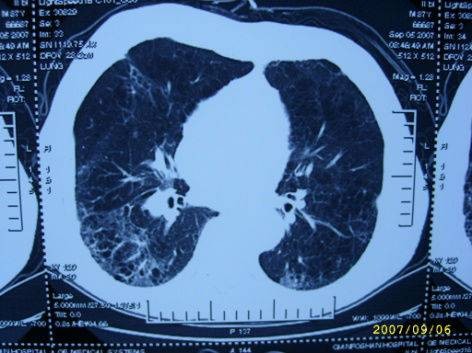

20天后,患者胸水消失,肺部炎症减轻、心影缩小,症状明显好转出院。

治疗后